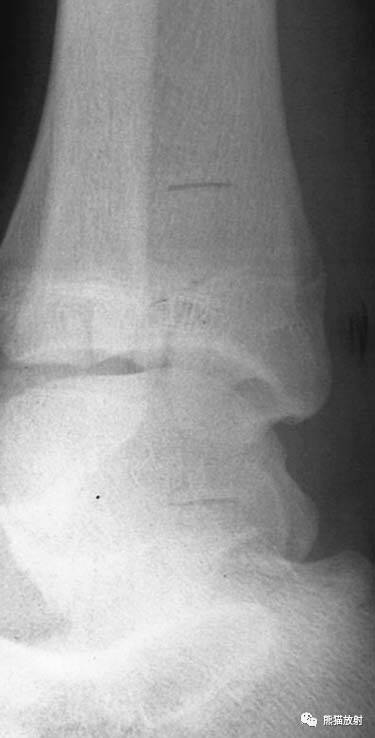

Salter-Harris III型:骨折累及骺板及骨骺,属于关节内骨折,可导致生长停滞。

Salter-Harris IV型:骨折累及骺板、干骺端及骨骺,属于关节内骨折。

第三型(Ⅲ型) 骨骺骨折。属于关节内骨折,骨折线从关节面开始穿过骨骺,再平行横越部分骺板的肥大层。该型占骨骺损伤的4%。多发生在胫骨远端内侧或外侧和肱骨远端外侧。无移位关节面平整者预后良好,有移位者需切开复位内固定,—般移位超过2mm者既是切开复位内固定的适应证。

第四型(Ⅳ型) 骨骺和干骺端骨折。该型也较多见,仅次于第二型,占30.2%;骨折线呈斜形贯穿骨骺、骺板及干骺端,由于骨折线同过生长板全层,所以容易引起生长发育障碍和关节畸形,多见者为鱼尾状畸形。此型多见于10岁以下小儿的肱骨外髁及年龄较大儿童的胫骨远端,此型必须切开复位及内固定。